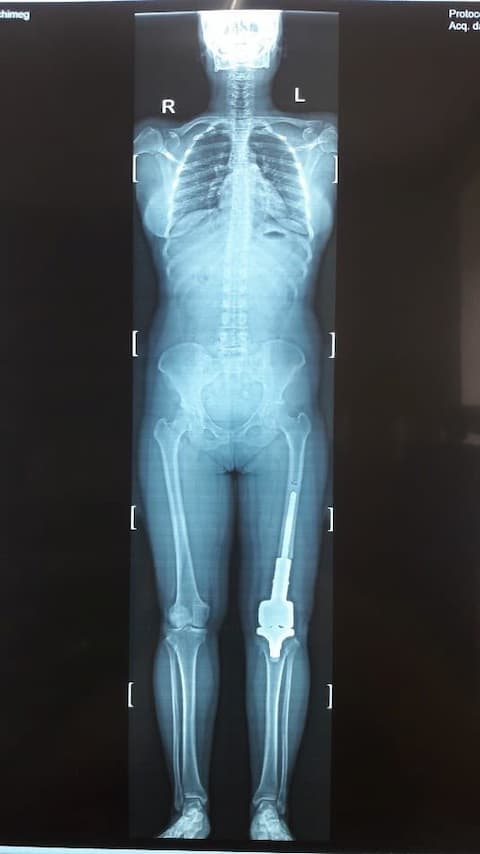

Б. Бүтэн биеийн рентген зураг

Зураг 2. Мэс заслын дараах рентген зураг

Хавдрын улмаасмэс хийлгэсэнөвчтөнгүүд мэс заслын дараа 2-3 хоногийн дотор шууд гишгэж явж, мөчдийн үйл ажиллагаа хурдан сэргэж эхний 1 сард үений хөдөлгөөний далайц хэвийн болсон .